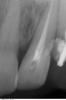

Мaxim Опубликовано 27 апреля, 2013 Поделиться Опубликовано 27 апреля, 2013 Уважаемые коллеги, подскажите как бы кто поступил в данной ситуации:21 наружняя резорбция, в канале цемент, при попытке ревизии выскочили в резорбцию, инструмент заклинил и остался. В канале Vitapex, последние 2 мм не пройдены.У нас варианта 2:1.Пломбировка альфа-гуттой, хирургическим путем извлечь инструмент, MTA, остеопластический материал и под наблюдение.2..Пломбировка альфа-гуттой, резекция,MTA, остеопластический материал и под наблюдение.Снимки. Прикрепленные изображения Ссылка на комментарий